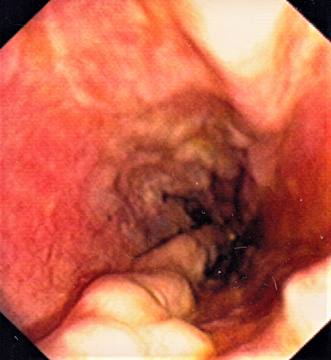

Oesophageal Varices in Banti´s syndrome

Oesophageal Varices in Banti´s syndrome.